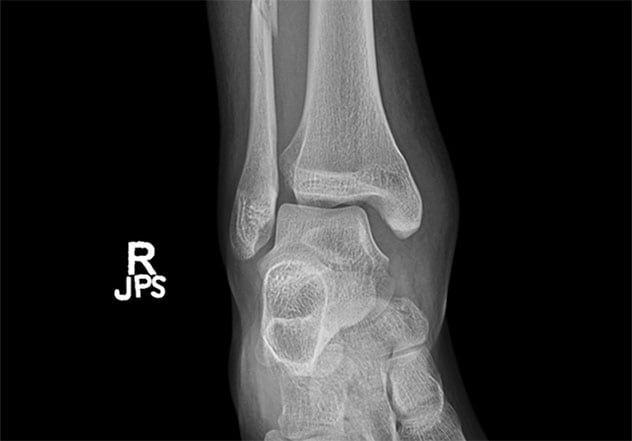

Ankle injuries: Seeking stability and a return to activity Aug. 06, 2021 Ankle injuries are fairly common and often debilitating, preventing individuals from resuming their normal levels of activity. And treatment modalities are evolving. At Mayo Clinic, orthopedic surgeons specializing in trauma take a personalized approach for patients of all ages and activity levels. "We have a very high volume of ankle fractures — up to 250 patients a year — with many seen during the winter when people slip and fall on ice," says Brandon J. Yuan, M.D., an orthopedic surgeon at Mayo Clinic in Rochester, Minnesota, with fellowship training in trauma. One unresolved issue in ankle fracture care is the need for fixation of the posterior malleolus during surgical fixation of ankle fractures, particularly when the fragment is small. Mayo Clinic is launching a clinical trial to evaluate operative versus nonoperative interventions for individuals with posterior malleolar fractures that involve less than 25% of the articular surface. Increasing attention is also being paid to the long-term stability of an individual's ankle after treatment for fracture. "We are focusing more on the role of the deltoid ligament. For some patients, deltoid repair is important to providing ankle stability," Dr. Yuan says. Ankle fracture with syndesmotic injury Enlarge image Close Ankle fracture with syndesmotic injury Ankle fracture with syndesmotic injury The radiograph demonstrates an unstable ankle fracture with a syndesmotic injury. Postoperative follow-up radiograph Enlarge image Close Postoperative follow-up radiograph Postoperative follow-up radiograph Postoperative follow-up radiograph demonstrates successful fracture fixation and syndesmotic repair. Long-term follow-up radiograph Enlarge image Close Long-term follow-up radiograph Long-term follow-up radiograph Long-term follow-up radiograph demonstrates successful fracture fixation and syndesmotic repair. Treatment modalities are also evolving for the syndesmosis. "Our thinking has shifted. We're focusing more on the rotational and translational instability associated with the syndesmosis, and the role that suture fixation or ligament repair can have in restoring normal motion, as opposed to screw fixation," Dr. Yuan says. "Our goal is for patients to get back to what feels like a normal ankle, especially because syndesmotic injuries are common and occur in people who are younger and of working age." As a major orthopedic surgery center, Mayo Clinic has physical therapists with extensive experience with ankle rehabilitation. "A multidisciplinary approach is key to helping patients regain function," Dr. Yuan says. "Our care starts with orthopedic traumatologists but continues through all aspects of the patient's medical care and recovery." For more informationClinical trials: A Study to Evaluate Operative versus Non-operative Intervention of Posterior Malleolar Fractures Involving Less than 25% of the Articular Surface. Mayo Clinic. Receive Mayo Clinic news in your inbox. Sign up MAC-20517737 Medical Professionals Ankle injuries: Seeking stability and a return to activity